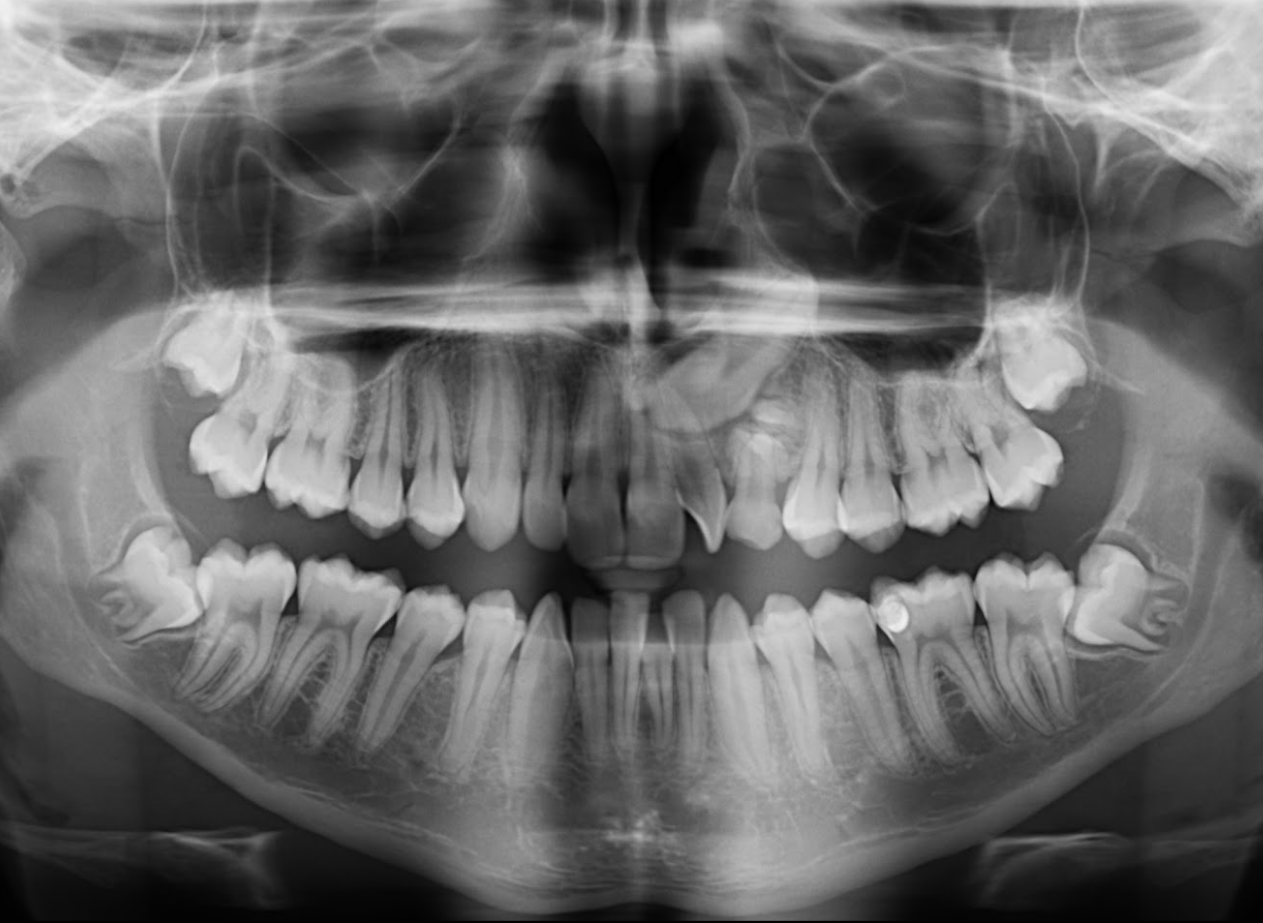

A la evaluación de la tomografía volumétrica (CBCT) en los cortes axiales (Figura 2) y transaxiales (Figura 3), se aprecia múltiples dentículos circunscrito de un halo hipodenso, localizada en palatino del tercio apical y medio de pieza 63, que ocasiona el desplazamiento de la pieza 23 hacia cefálico y adelgazamiento de la tabla ósea palatina.

CORTES AXIALES